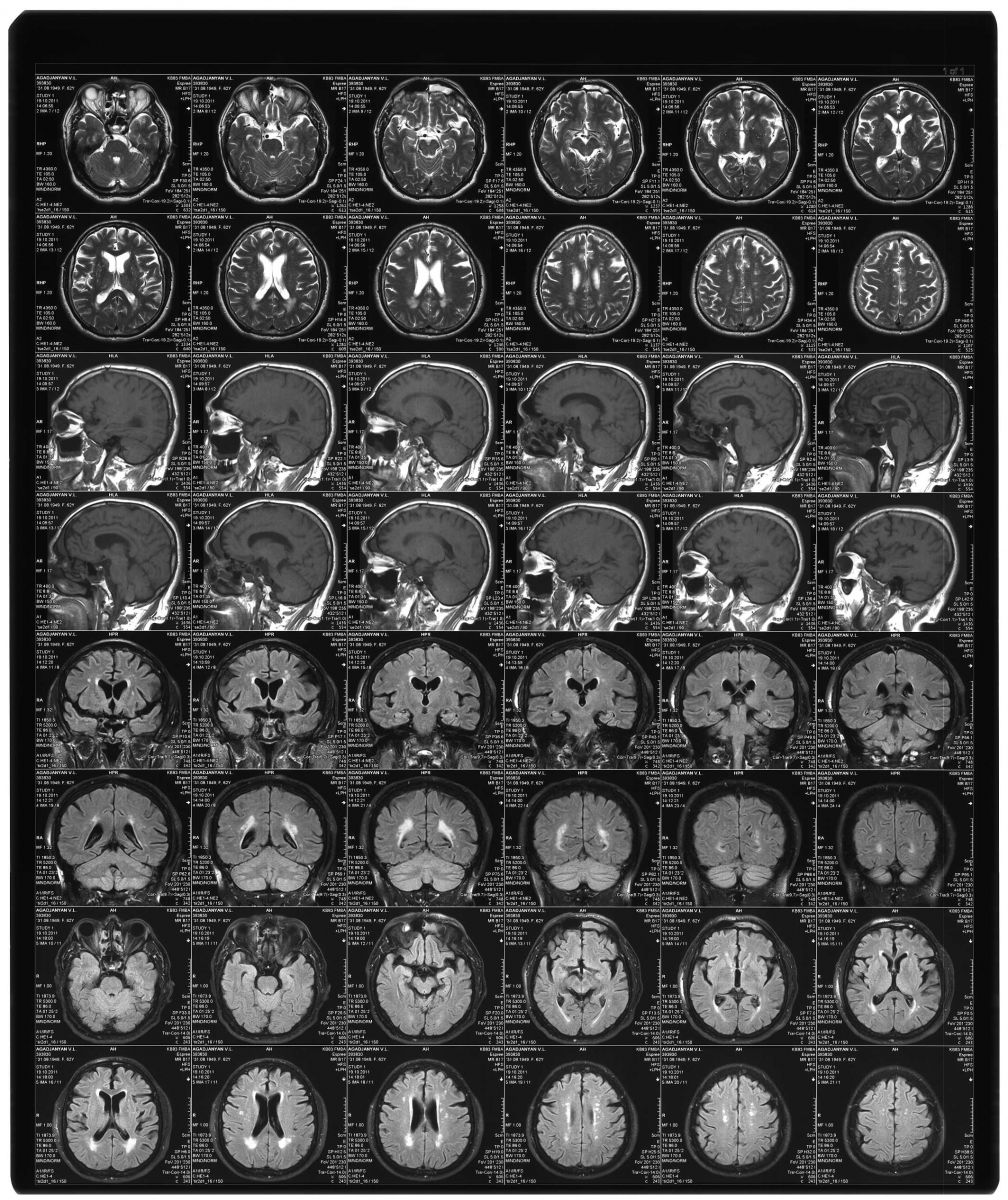

Сканирование рентгеновских снимков

Сканирование рентгеновсих снимков может понадобиться для удаленной консультации или подготовки документов для назначения лечения.

Так же оцифрованные рентгеновские снимки удобней хранить и индексировать самим медицинским учреждениям. Это позволяет сократить время поиска необходимого файла и является первым шагом для перехода на электронную медицинскую отчетностью

Примеры сканирования рентгеновских снимков:

Лист КТ

Увеличенный фрагмент